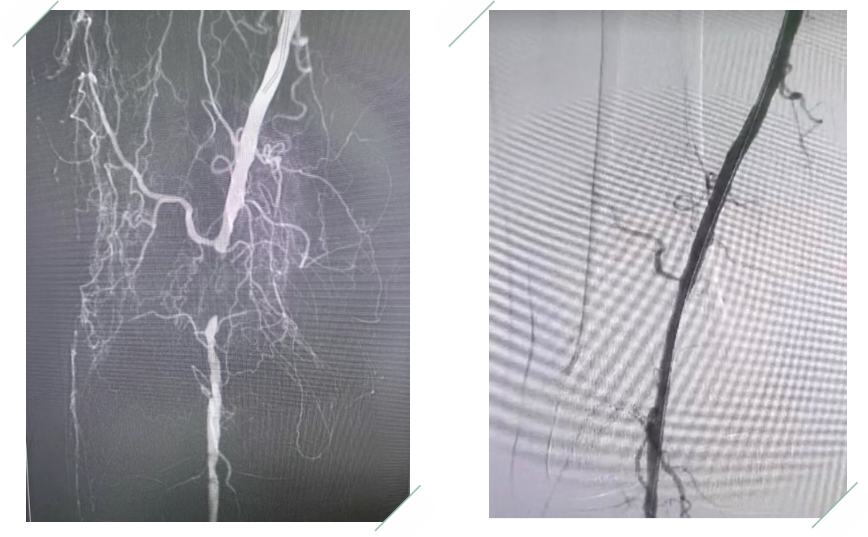

该患者因右下肢凉、麻、痛2年,急性加重10余天,于2025年10月7日就诊保定市第一医院心胸血管外科,诊断为下肢动脉硬化闭塞症。张大爷病情危急,心胸血管外科团队迅速响应,王首旭主任、刘宝顺医生全面评估,凭借丰富的临床经验和精湛的介入治疗技术,为患者制定了精准的治疗方案。手术中医生们全神贯注、配合默契,成功为患者解除了病痛危机。